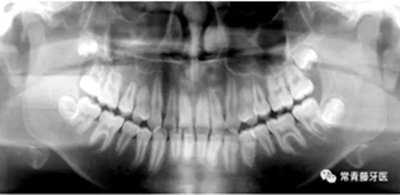

影像學(xué)檢查

無(wú)缺牙及多生牙,雙側(cè)下頜升支高度相等,智齒未萌。

頭影測(cè)量顯示為骨性Ⅲ類高角患者。